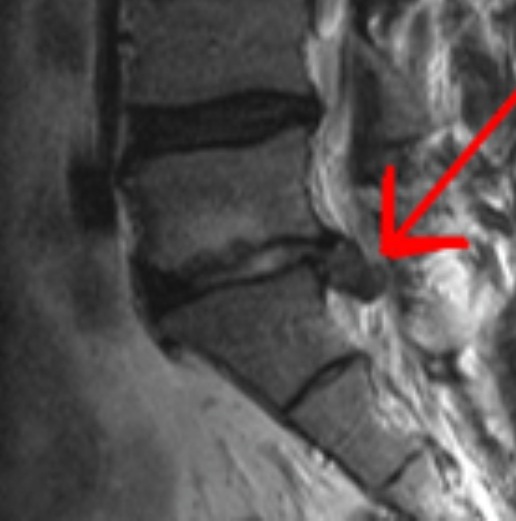

HNP (hernia del núcleo pulposo)

Dolor de espalda, radicular, ciática déficit neurológico asociado a compresión de raíz.

Estenosis lumbar o cervical, claudicación neurógena y planificación de descompresión dirigida.

Correlación clínico-radiológica y decisión de descompresión según síntomas y hallazgos.